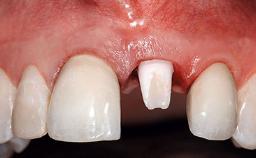

Replacement of a Failing Restored Upper Right Central Incisor, Ridge Preservation and Early Placement of an RC Bone Level Implant

A 23-year-old female, healthy and non-smoking patient had had tooth 11 temporarily restored following a trauma in adolescence. As the patient’s growth had since come to an end and the crown had fractured, she requested an implant-supported restoration of tooth 11. Moreover, the contralateral tooth 21 presented an old composite restoration at the mesial incisal edge. The periodontal tissues were healthy with periodontal probing depth values below 3 mm, but some inflammation was observed around the semi-submerged root of tooth 11.